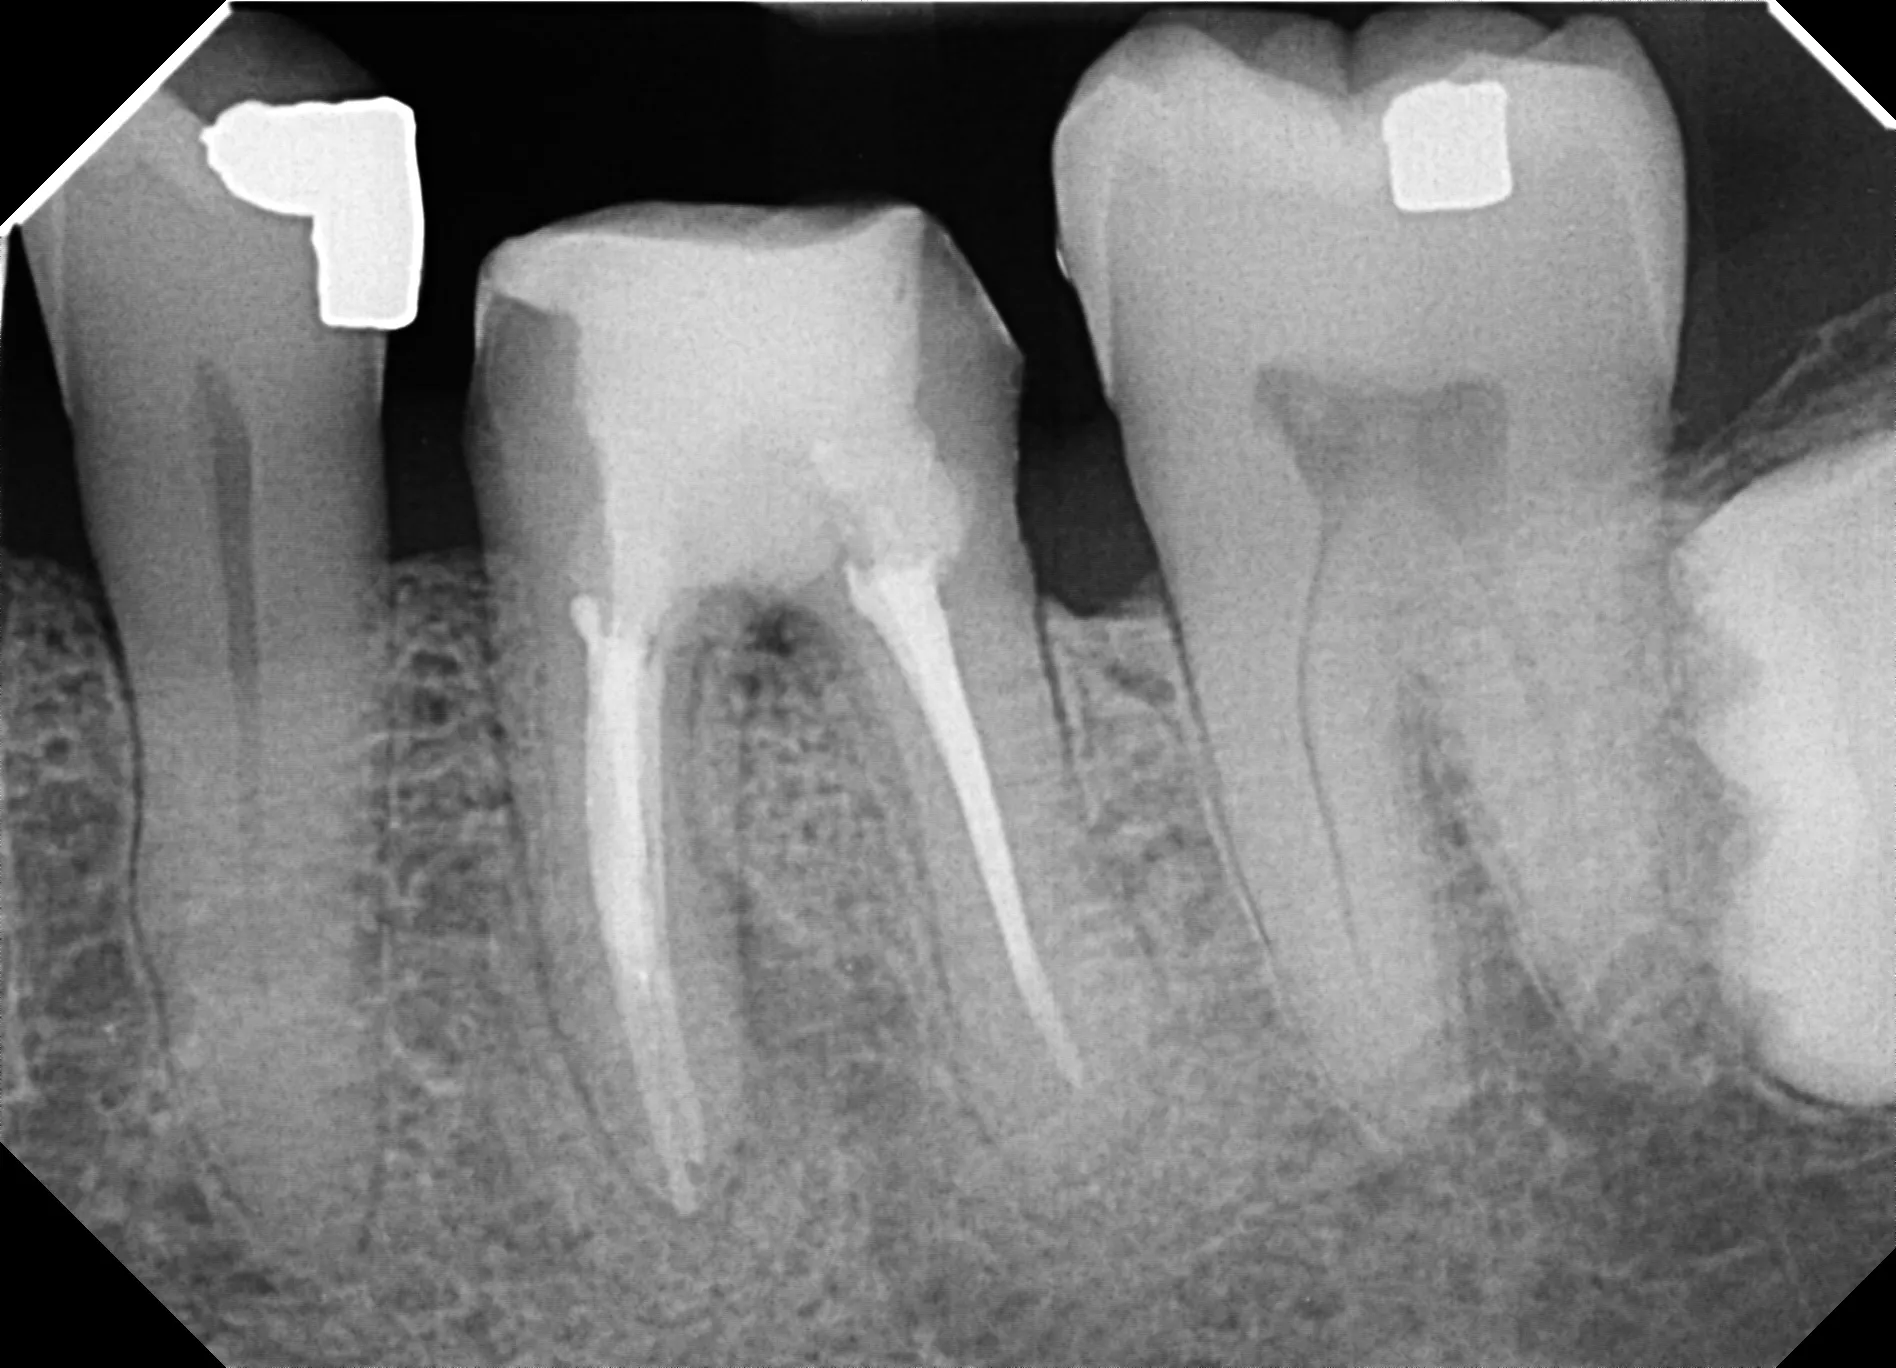

The referring dentist had searched for the distal canal, drilled too far lingually, and created a 2mm perforation directly into the furcation. The patient presented with active bleeding from the perforation site and understandable anxiety about losing the tooth.

3. MTA Placement: Pack mineral trioxide aggregate into perforation defect under high magnification

At 3-year follow-up, this tooth shows excellent healing:

• Radiographic evidence of bone maintenance at perforation site

• Tooth functional with crown in place